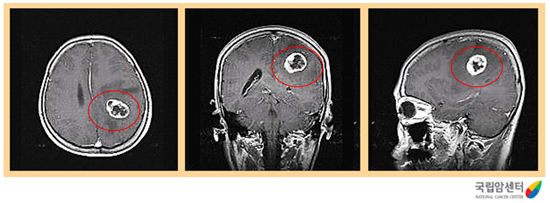

교모세포종의 뇌 자기공명영상촬영 소견

2009.12.16